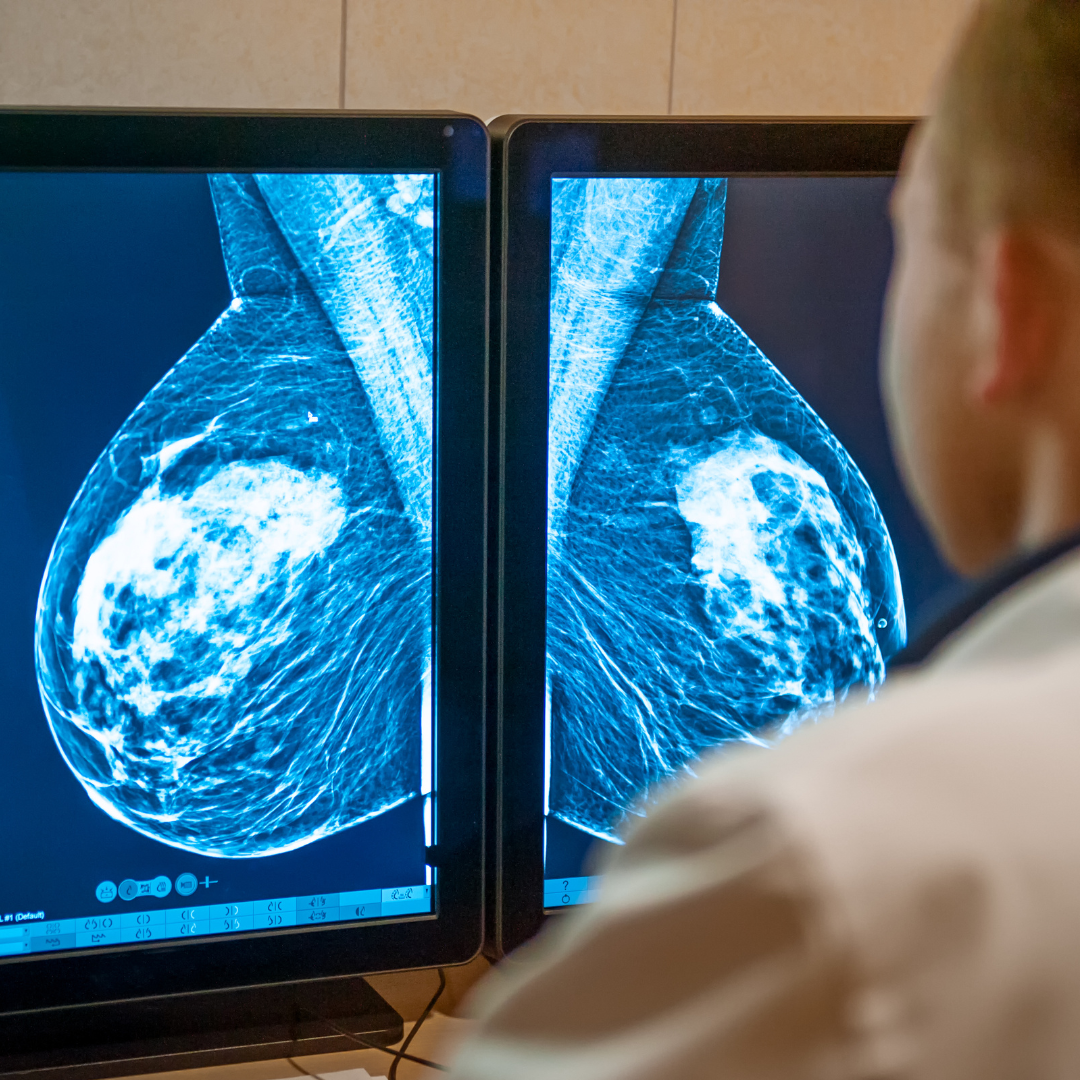

Breast Density 101

About 50% of women over 40 have dense breasts. Dense tissue is the amount of fibrous vs. fatty tissue in the breast. Dense breasts increase your risk of breast cancer by 4-6x, and cancer is harder to spot on mammograms in dense tissue. Learn more about breast density and why it increases your chances of breast cancer.

Mammograms 101

Did you know that dense breast tissue hides up to 50% of cancers on a mammogram? That means if you have dense breasts, your cancer could go undiagnosed. Learn more about dense breasts and other risk factors for breast cancer